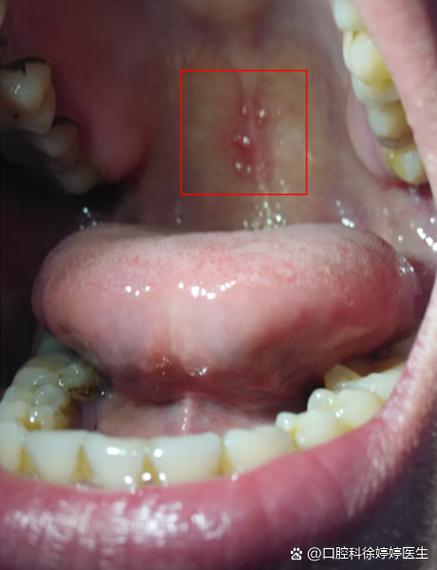

(图片来源网络,侵删)